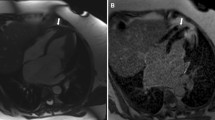

On the four-chamber view, the distance between the cutting edge of the tricuspid annulus with the RV free wall and the RV apex or a reference point outside the RV apex were measured in end-diastole (end-diastolic length (EDL)in or EDLout) and end-systole (end systolic length (ESL)in or ESLout). The point outside the RV apex was chosen in extension to the RV apex and had to stay unchanged at end-diastole and end-systole. In order to ensure that the reference point outside the RV apex stayed unchanged during end-systole, we left the curser at the point of the chosen reference point while scrolling from end-diastole to end-systole. TAPSEin (Fig. 1a, b) was defined as the difference between EDLin and ESL, TAPSEout (Fig. c, d) as the difference between EDLout and ESL. The RVFS was calculated as follows: RVFS (%) = [(EDLin –ESLin)/EDL in] × 100 [12].

Schematic figure of TAPSEin (Panel a and b) and TAPSEout (Panel c and d) measurement using a four-chamber cine image. Two separate reference lines are drawn in diastole (right ventricular end-diastolic length [RVEDL]) and systole (right ventricular end-systolic length [RVESL]) from the basal lateral tricuspid annulus to a reference point in the right ventricular apex: TAPSEin (Panel a and b) or a reference point outside the right ventricle: TAPSEout (Panel c and d) Abbreviations: TAPSE tricuspid annular systolic excursion